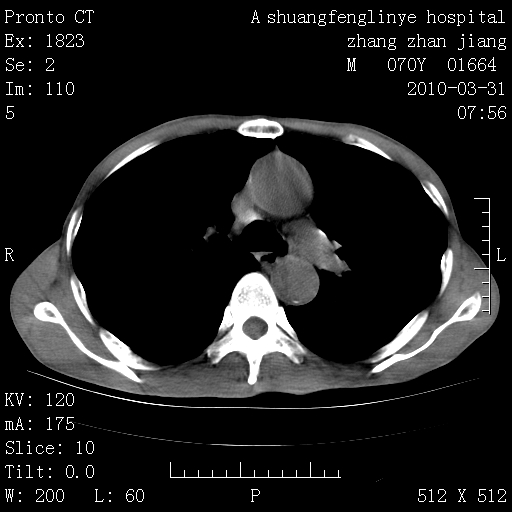

双上肺继发型tb并左上空洞形成,主动脉冠脉钙化。

1)两肺上叶继发性肺结核并左肺上叶空洞形成。2)冠状动脉及主动脉钙化。